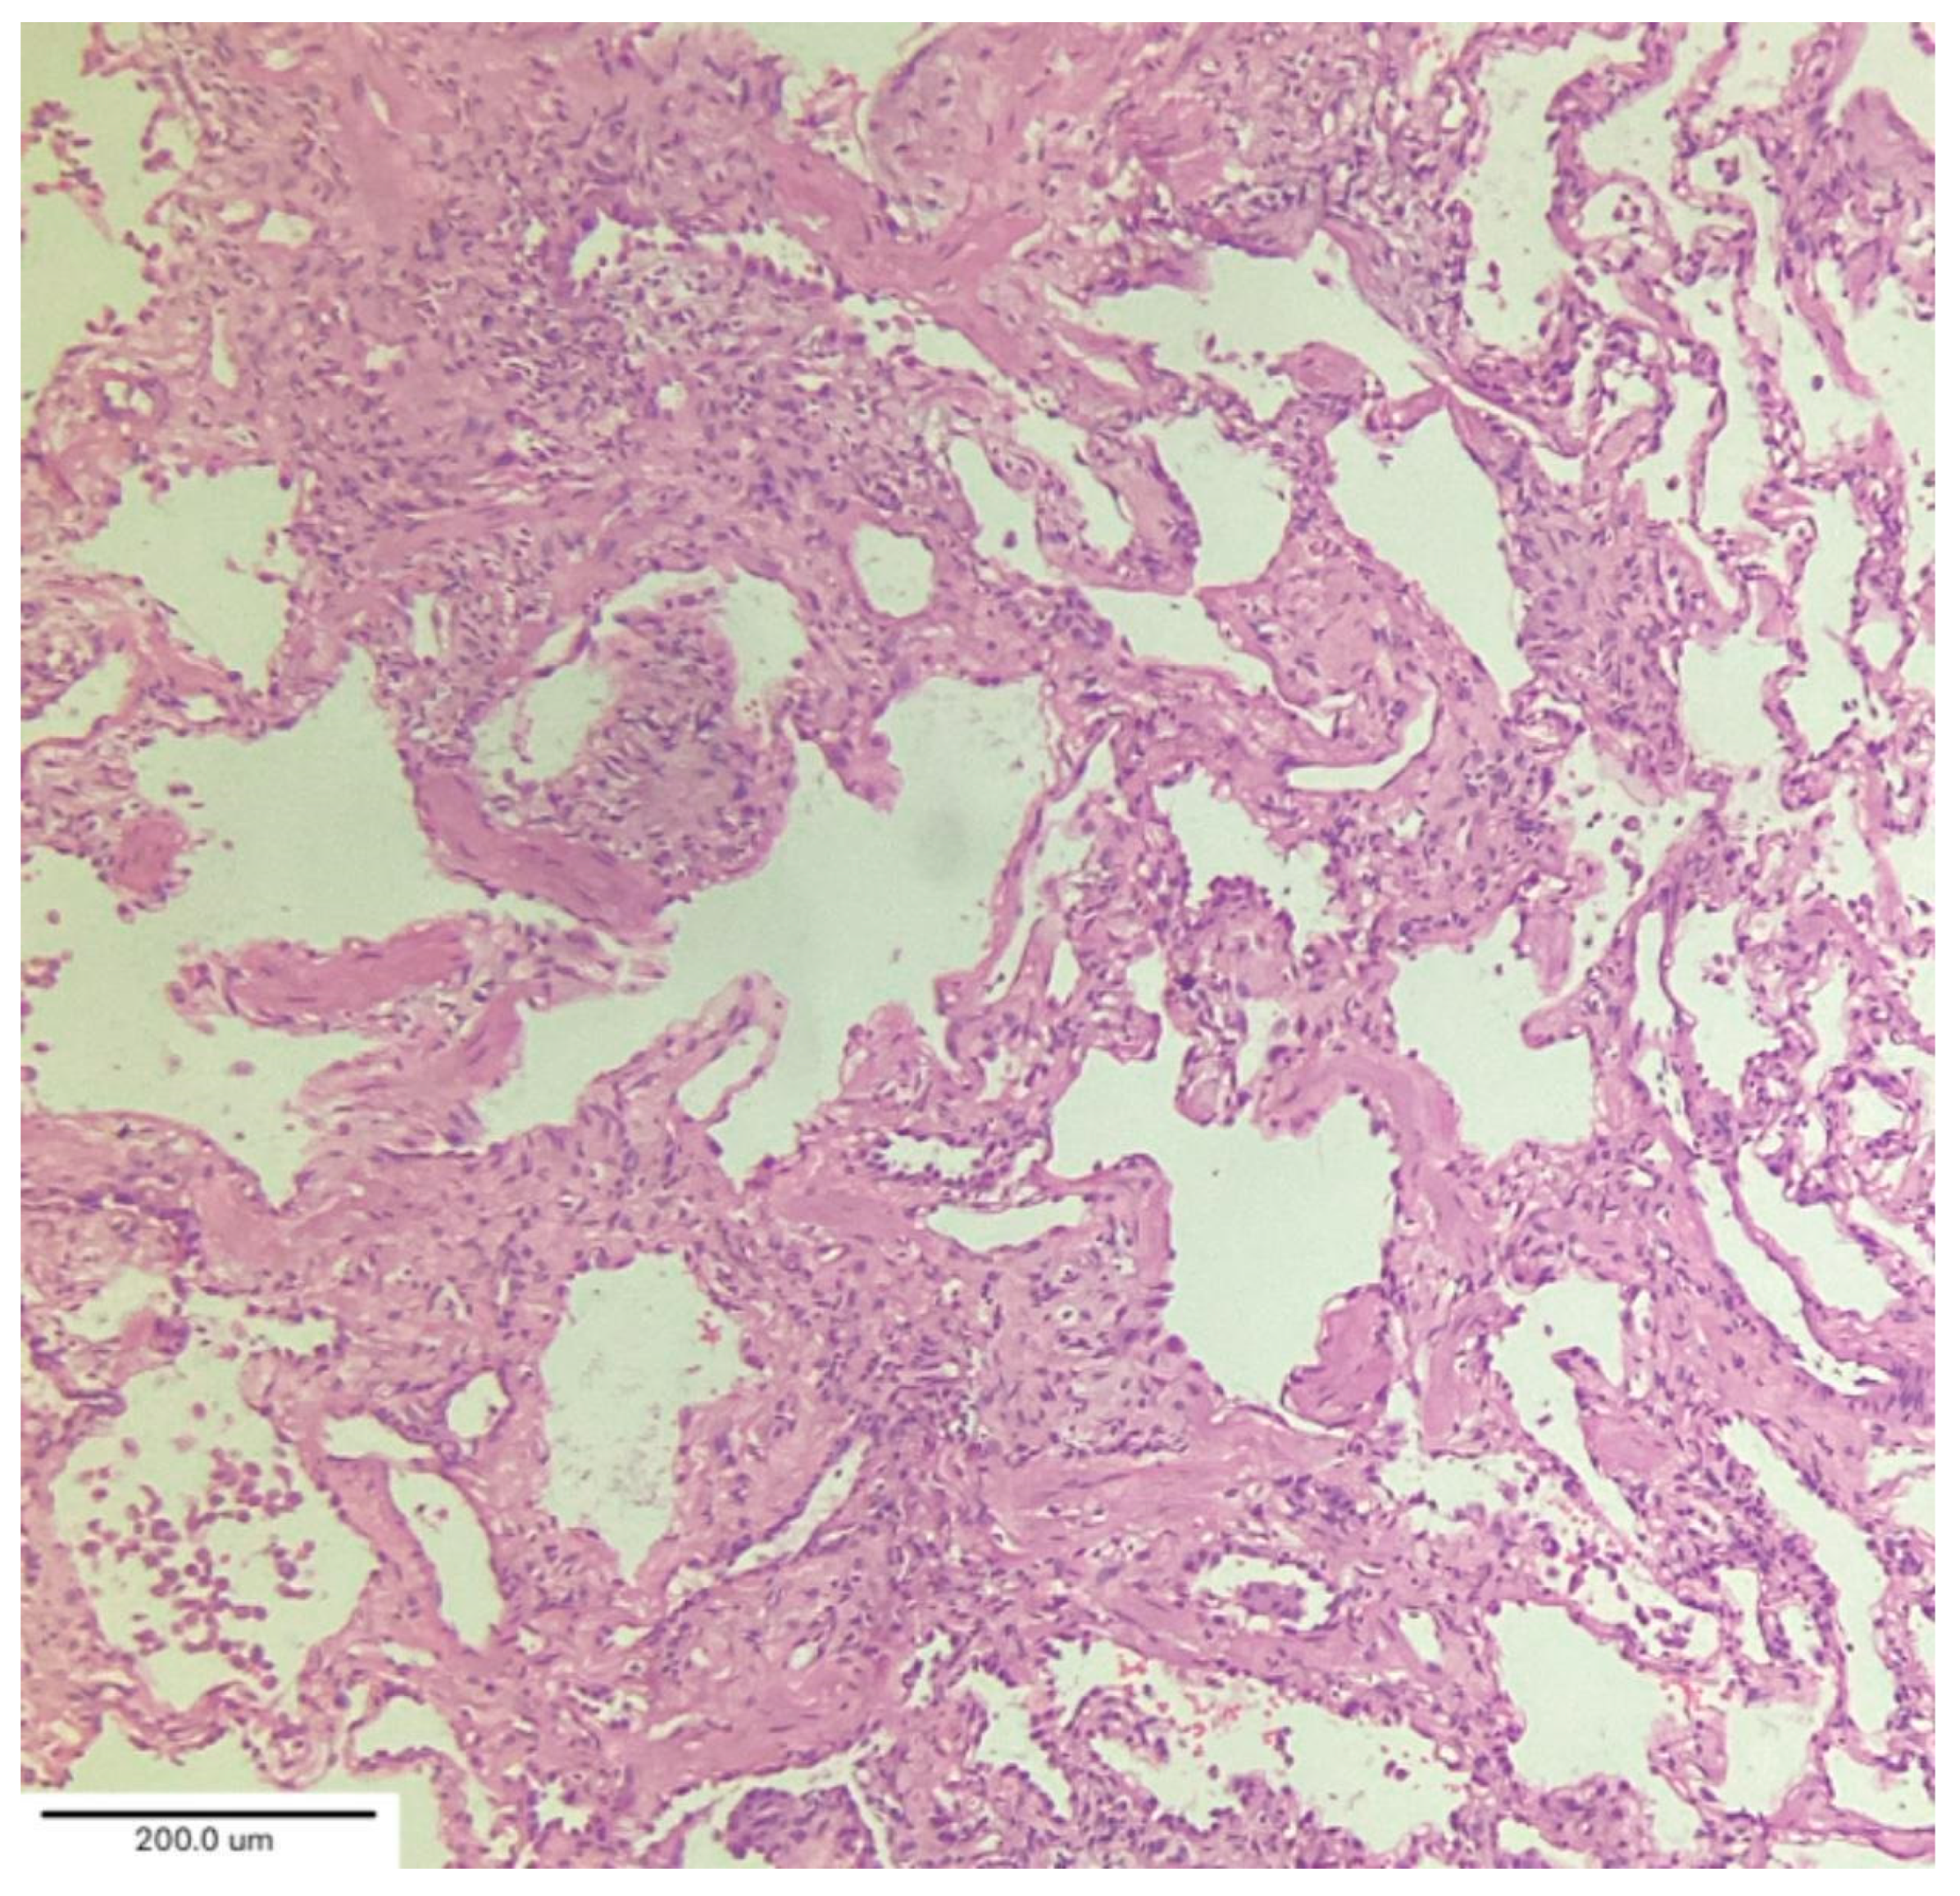

A case series by Aesif et al. [35] described the presence of diffuse interstitial fibrosis vaguely resembling an NSIP pattern (Figure 7) and areas of microscopic honeycombing in patients after a 4-month follow-up period. Fibroblastic foci were not observed in the biopsies. Incorporating biopsy findings into the post-COVID-19 multidisciplinary evaluation can help to identify key patient subgroups, understand the pathogenic mechanisms of ILD progression, and create better patient-specific treatment protocols that improve clinical outcomes. [36,37]

Figure 7. Diffuse interstitial fibrosis with nonspecific interstitial pneumonia pattern. Magnification: H&E ×100.